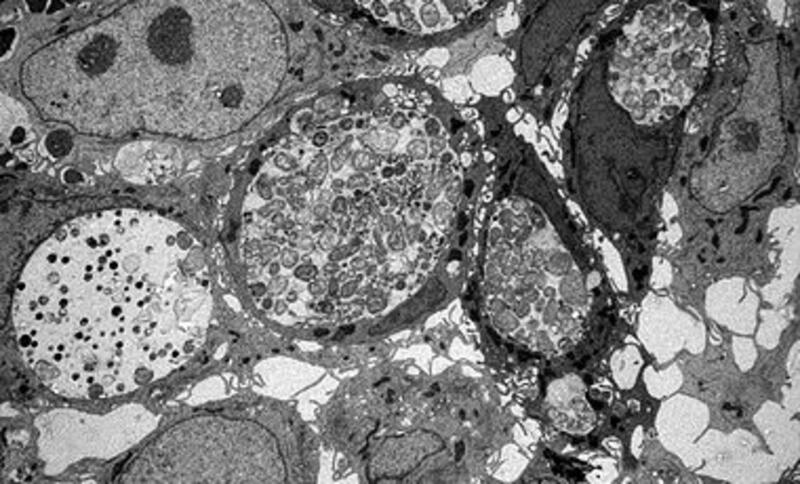

Sin embargo, cuando las clamidias acceden al intestino a través de la sangre, pueden infectar de manera muy eficiente. En estos casos, los investigadores identificaron repetidamente las formas persistentes de las bacterias, que se pueden reconocer fácilmente bajo el microscopio electrónico.